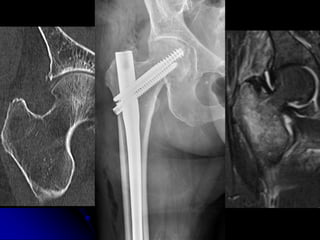

HIP FRACTURES